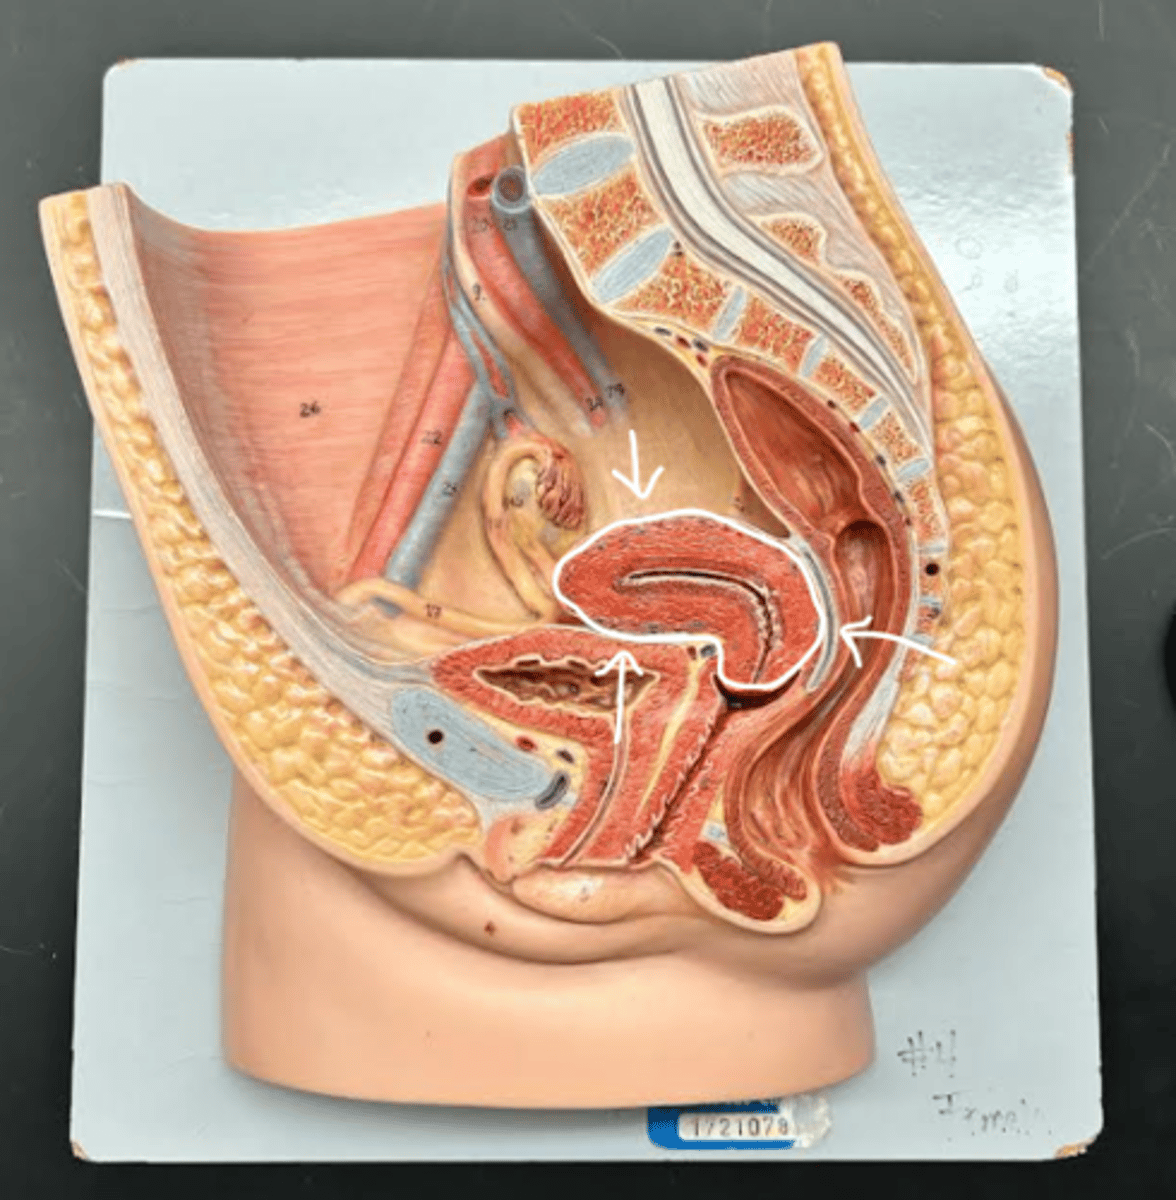

Vagina

Vaginal orifice

Hymen

Vaginal fornix

Ovary

Fallopian tube

Fimbriae

Infundibulum

Ampulla

Isthmus

Uterus

Perimetrium

Myometrium

Endometrium

Fundus

Body of uterus

Cervix

Internal os

Cervical canal

External os

External urethral orifice